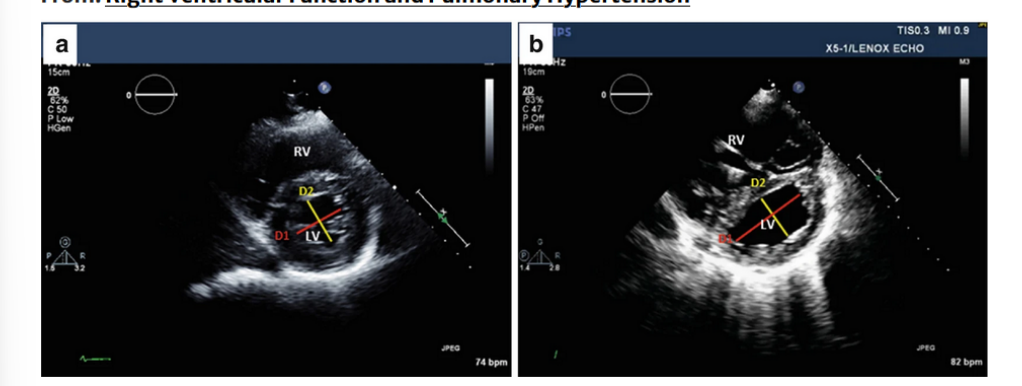

RV/LV interdependence-Eccentricity index. (a) Normal right and left ventricular morphology:

the left ventricle has a what shape configuration; the ratio of the what (D1) to the what (D2) is clost to what number?

Right ventricular overload, the LV takes a what shape, and then what flattens? and what dimension of the what is greater then the what?

RV/LV interdependence-Eccentricity index.

(a) Normal right and left ventricular morphology: the left ventricle has a round configuration; the ratio of the antero-posterior dimension (D1) to the septal-lateral dimension (D2) is close to

1. (b) Right ventricular overload, the LV takes a crescentshape, the interventricular septum flattens, and antero-posterior dimension of the left ventricle is greaterthan the septal-lateral